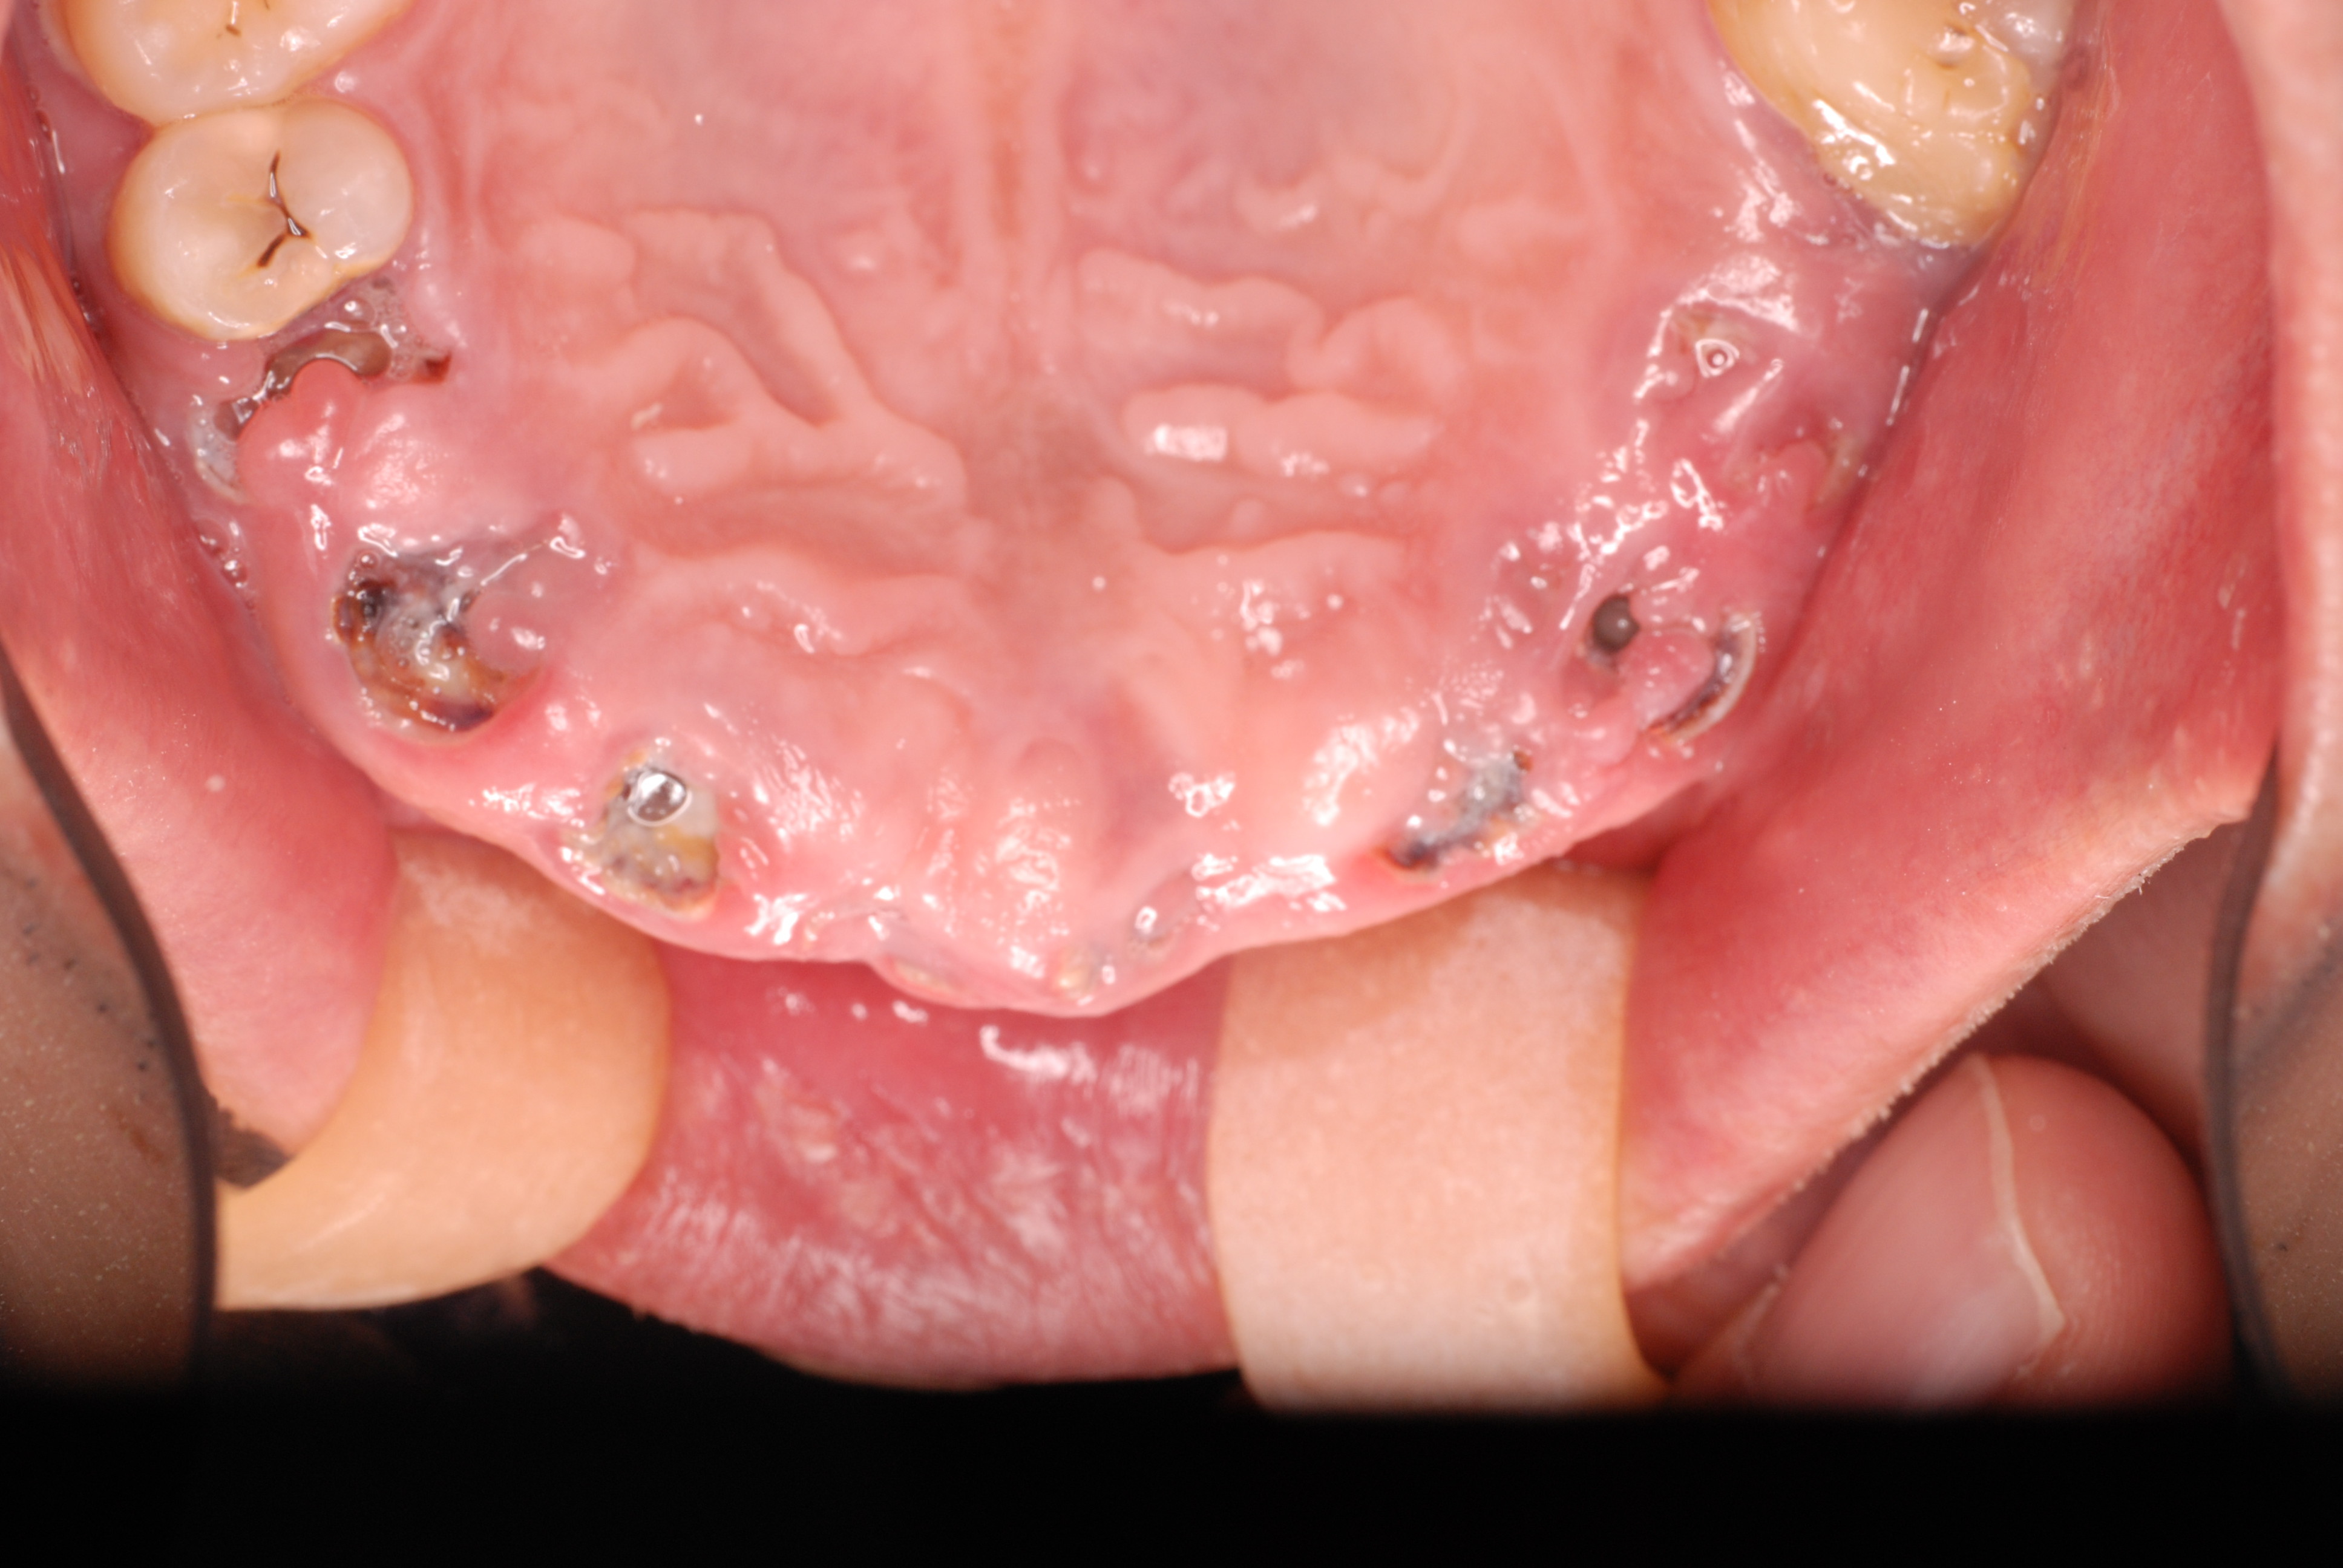

歯無しにならない長い話し

今回約1年近くかかった方のとりあえずの治療が終了しました。

最初の状態です。若いのにすぐ外れる入れ歯をいれていらっしゃいました。

DSC_0167DSC_0162

DSC_0166DSC_0165

DSC_0164

そしてひとまず終了した状態です。

DSC_0018DSC_0023

DSC_0027

このように綺麗になりましたが元の健康な状態になったのではないのです。ばい菌が歯の周りから採れていなければ元の木阿弥。

おそらく差し歯にもできず入れ歯かインプラントという人工歯根になる事でしょう。いやはやいくら費用がかかるのやら患者さんのことながらため息が出ます。

歯医者では病気を治していないことが多いのです。ただ詰めたり被せたりしているのに過ぎません。注意しないともっとひどいことになります。

そして、虫歯や歯周病、そして神経の処置は医療行為ですから誰でも100%うまくいくかというと、うまくいっていないことが多いのです。医療行為は難しいのです。良い歯の医者に当たる事を祈ります。

歯に何かを被せることは医者のやることではなくお口の大工さんがやることなのです。ですから歯医者は、大工と医者を同時にやっていることになりますね。

歯医者から口腔科の医師へ脱皮しなければなりません。日々精進あるのみ!